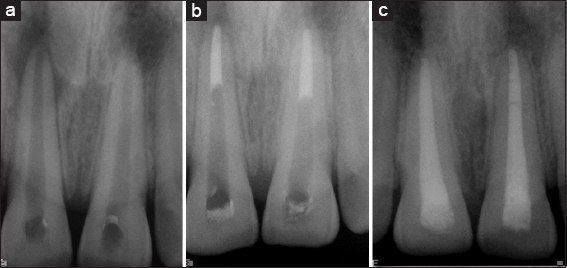

Group II: (Mineral trioxide aggregate apexification + platelet-rich plasma on a collagen sponge)

Under Rubber dam isolation, access preparation was done in necrotic immature permanent upper anterior of 18 patients (18 roots). In the cases subjected to revascularization, local anesthesia without a vasoconstrictor was administered at the first visit, with preparation of an access cavity, working length instrumentation, irrigation with 1.5%–2.5% sodium hypochlorite and 17% ethylenediamine tetraacetic acid, Canals were copiously irrigated with 2.5% sodium hypochlorite, and minimal instrumentation was done to prevent the weakening of the lateral dentinal walls. The TAP was placed as an inter-appointment medicament in the dried canals, and the coronal access was sealed with intermediate restorative material for 4 weeks. Moreover, patients were recalled after 4 weeks of treatment. In Group II PRP + collagen was introduced as a scaffold and pushed toward the apical area using endodontic pluggers and then MTA apexification was done using messing gun to form the 3–4 mm of the apical plug. It was obturated using gutta-percha and AH Plus sealer. The tooth was permanently restored with adhesive restoration during the same visit [Figure 2a-c].

thumb

Figure 2: (a) Preoperative, (b) Mineral trioxide aggregate + Platelet rich plasma, (c) 1 year follow-up